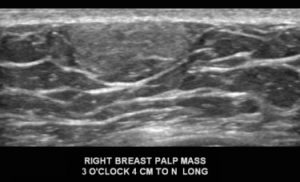

With the mammogram appearing negative, a diagnostic ultrasound was performed. What is the diagnosis?

Explanation: This is a circumscribed, oval, hyperechoic mass, which is consistent with a lipoma. They have the same imaging appearance in males and females. They may appear as circumscribed fat-containing masses on the mammogram, particularly if the patient has a lot of fibroglandular tissue. Since this male’s breast is composed predominantly of fat density, the lipoma cannot be easily discerned on the mammogram. On ultrasound, a lipoma (arrows) is either isoechoic or slightly hyperechoic to the surrounding subcutaneous fat (*). Lipomas are benign and when correctly identified on imaging, they do not require further follow-up.

D. Lipoma; BI-RADS 2 (Benign)